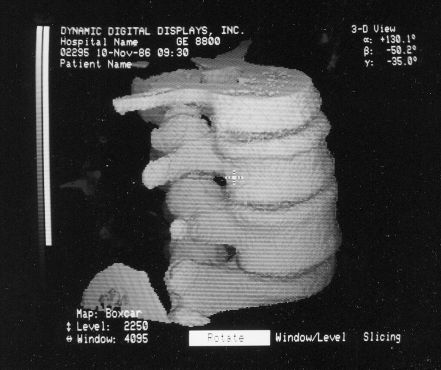

Here are typical examples of VoxelQ displays. These are mostly only windows, not the full screen which is more along the lines of the last block of AcQSim photos.

VoxelQ Multiplanar Reformatting (Axial, Saggital, Coronal, Curved)

VoxelQ Shaded Surface

VoxelQ Volume Rendering

While the VPP and Voxelscopes I and II rendered "back-to-front" to implement hidden surface removal, the redesigned VoxelQ hardware was optimized for ray tracing with volume rendering capabilities. VQ projected a ray from each pixel on the display back through the object and was able to perform computations along the way. An innovative sub-voxel search algorithm rendered much more realistic surfaces using relatively simple surface shading algorithms. Even Anthony was impressed with the image quality when this technique was first simulated in software with the intent of incorporating it into the microcode - and he was most familiar what else was being done in software, which could render the best images since there were fewer time constraints. In addition to hidden surface removal and gradient shading, this approach supports various forms of transparency with perspective enabling the simulation of X-ray views ("reprojection") as well as rendering translucent organs. Many of the changes were implemented in microcode with relatively small changes to the actual hardware. But the key innovation that differentiated VoxelQ from the machines before it was the "Object Resampling Memory" (ORM) which generated tri-linearly interpolated voxel data based on full 3-D coordinates. Essentially, the eight adjacent voxels closest to the specified coordinate in the original dataset were accessed simultaneously and an interpolated result was computed auto-magically. For successive coordinates that were close together (as they would be for ray tracing), the effective throughput could approach 10 million tri-linearly interpolated voxels per second. The ORM was the only totally new custom board and replaced the MicroVAX memory.

Shading of the rendered objects is essential to the perception of 3-D depth in a static display of a single image (no stereo). Motion parallax also contributes to this but only if the update rate is high enough. The VPP only had "depth shading", whereby each pixel's value was modified by distance from the viewer. Subsequent machines used "gradient shading" which also calculated the local rate-of-change of the surface to modulate the pixel intensity. While this was not photo-realistic, the overall effect was quite satisfactory at a much lower computational cost. And with the tri-linearly interpolated voxels, the result was actually quite impressive.

Shading for Ray Tracing (Portion of Cervical Spine)